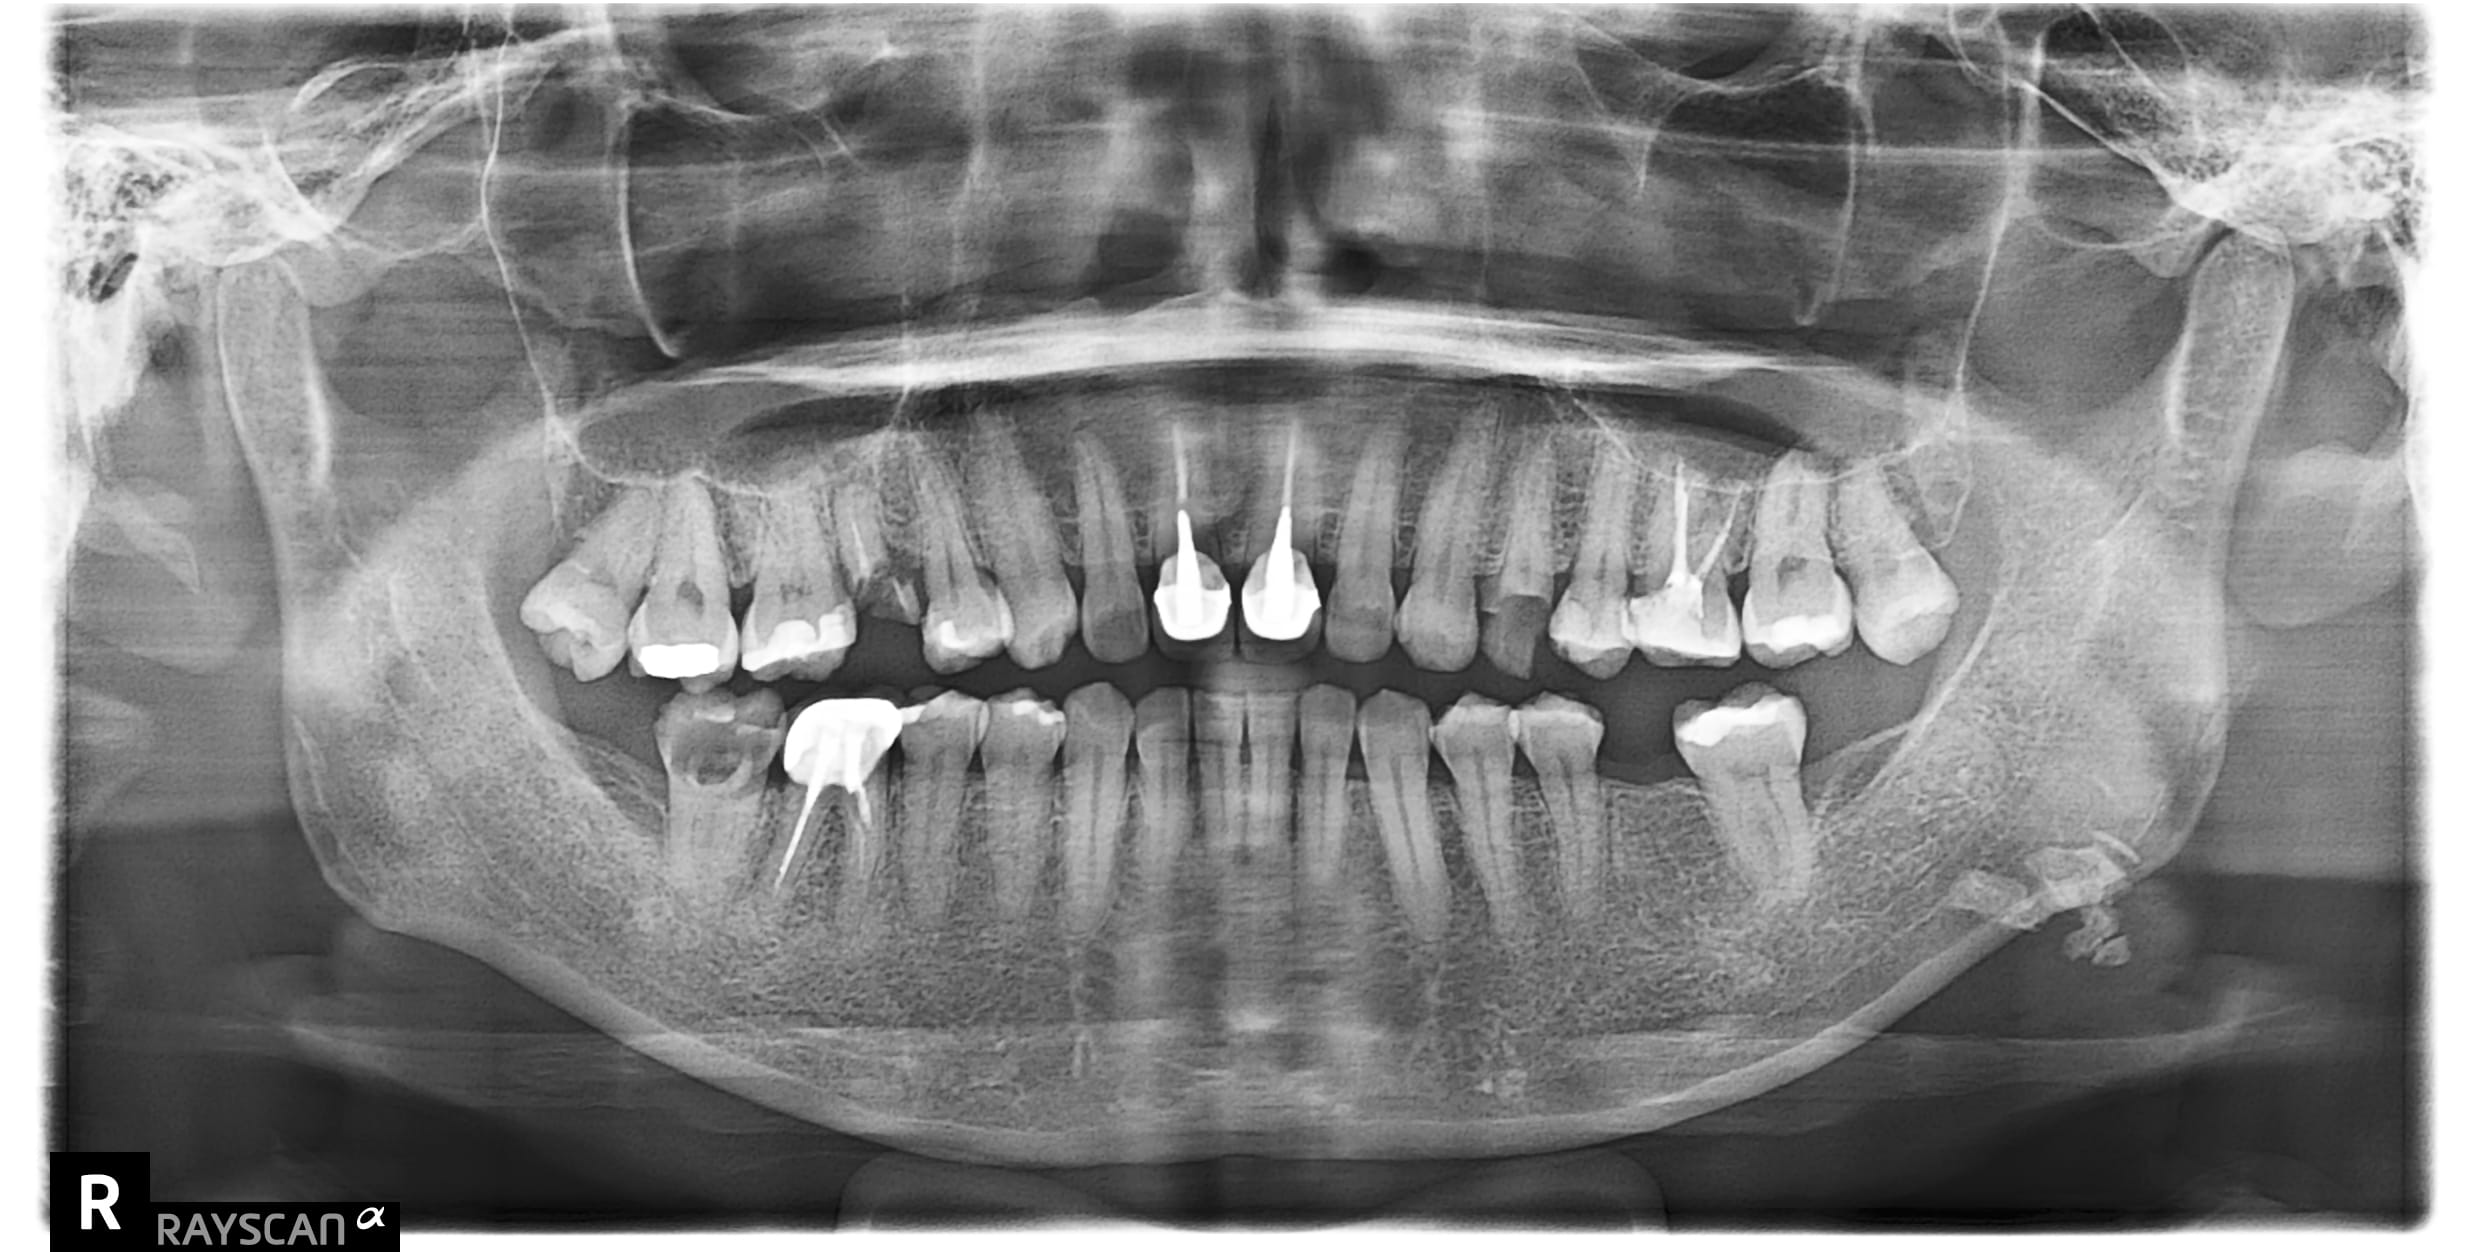

x先生左下第二小臼齒舊牙冠二次蛀牙斷掉,並影響到咬合問題 假牙不密合導致再蛀齒質脆弱咬東西斷,建議即